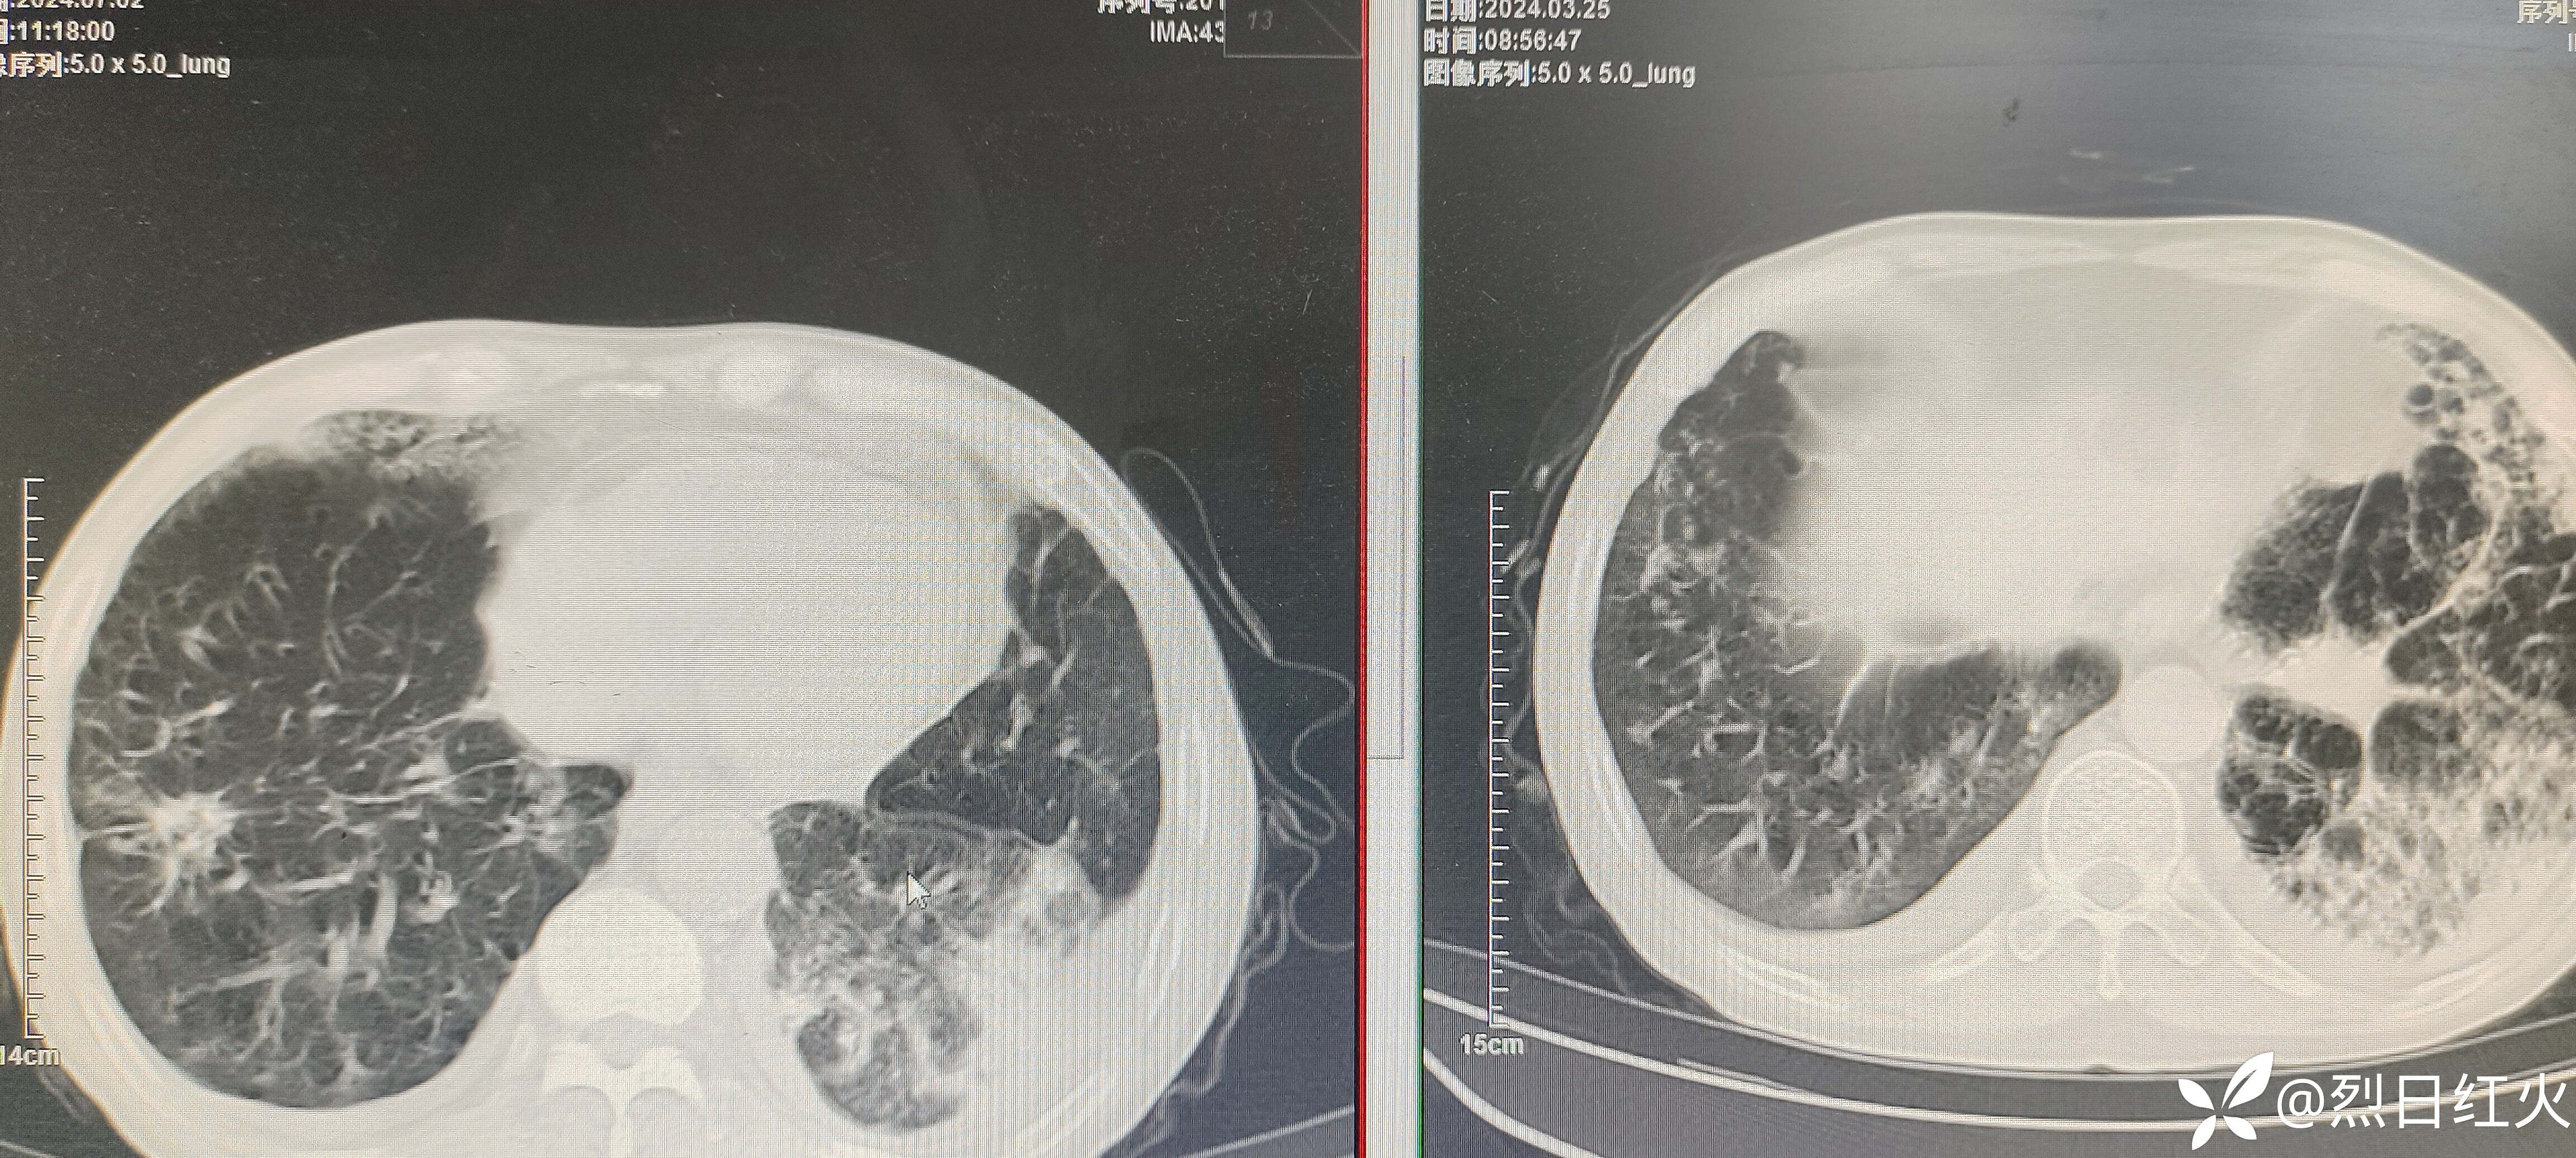

该病历患者入院后病情缓解,以后症状逐渐加重,治疗经过有不足之处望指正!2024-07-02复查胸部CT与2024-03-25胸部CT对比,病灶较前明显吸收。如下图:

复查胸部CT

CT平扫:双侧胸廓对称,双肺纹理增多、紊乱,肺野透光度增强,双肺见多发小结节样及条索状稍高密度影,边界清楚,双肺呈对称性分布,以双肺上叶中内带为著,双肺见多发斑片状稍高密度影,边界欠清,纵隔气管居中,纵隔内未见明显肿大淋巴结影,心影未见明显增大,心包未见明显增厚,双侧胸腔见弧形稍低密度影,胸壁软组织未见明显异常,扫描范围内:肝内见多发圆形低密度影,CT值约6HU,较大直径约2.8cm。

1、右肺中叶、下叶及左肺感染性病变治疗后复查,与2024年3月20日CT对比,病灶有所增加。

2、慢性支气管炎、肺气肿。

3、双肺改变,请结合其职业史,建议进一步检查,除外尘肺。

4、双侧胸腔积液。

5、肝内多发囊性占位性病变,建议上腹部CT平扫。